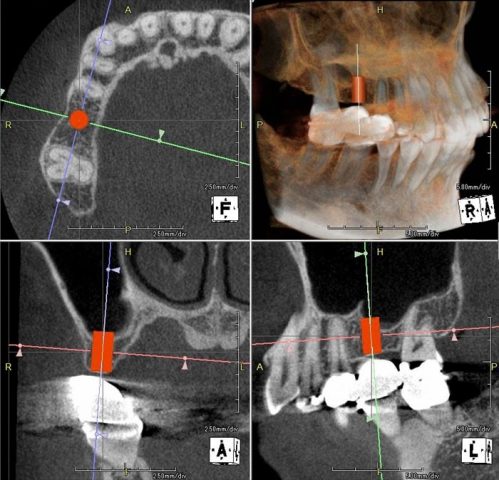

上下歯列模型の印象採得とフェイスボウトランスファーをいつものように行い、下顎の回転半径の近似値を得ます。

半調節性咬合器に上下歯列模型をフェイスボウを用いてマウントしました。

模型とCTデータを重ねて埋入ポジションを決定します。

術者の脳内イメージを作成する行程です。

サージカルステント(ドリルガイド)を製作してオペ前の準備は完了です。